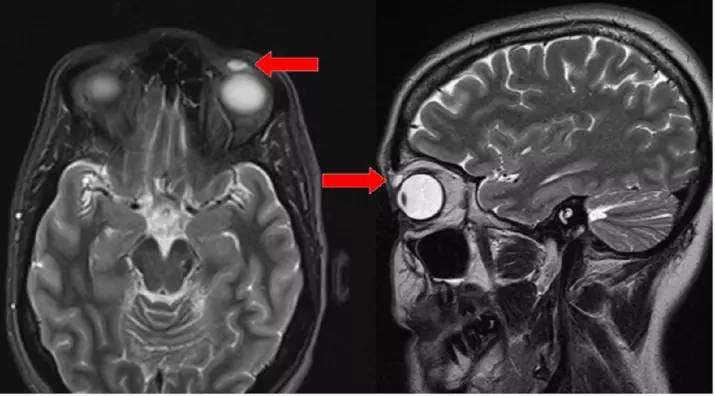

應該每個帶隱形眼鏡的人都有想過這個問題:萬一這東西卡在我眼裡怎麼辦?最近英國一名42歲女子就發生這樣